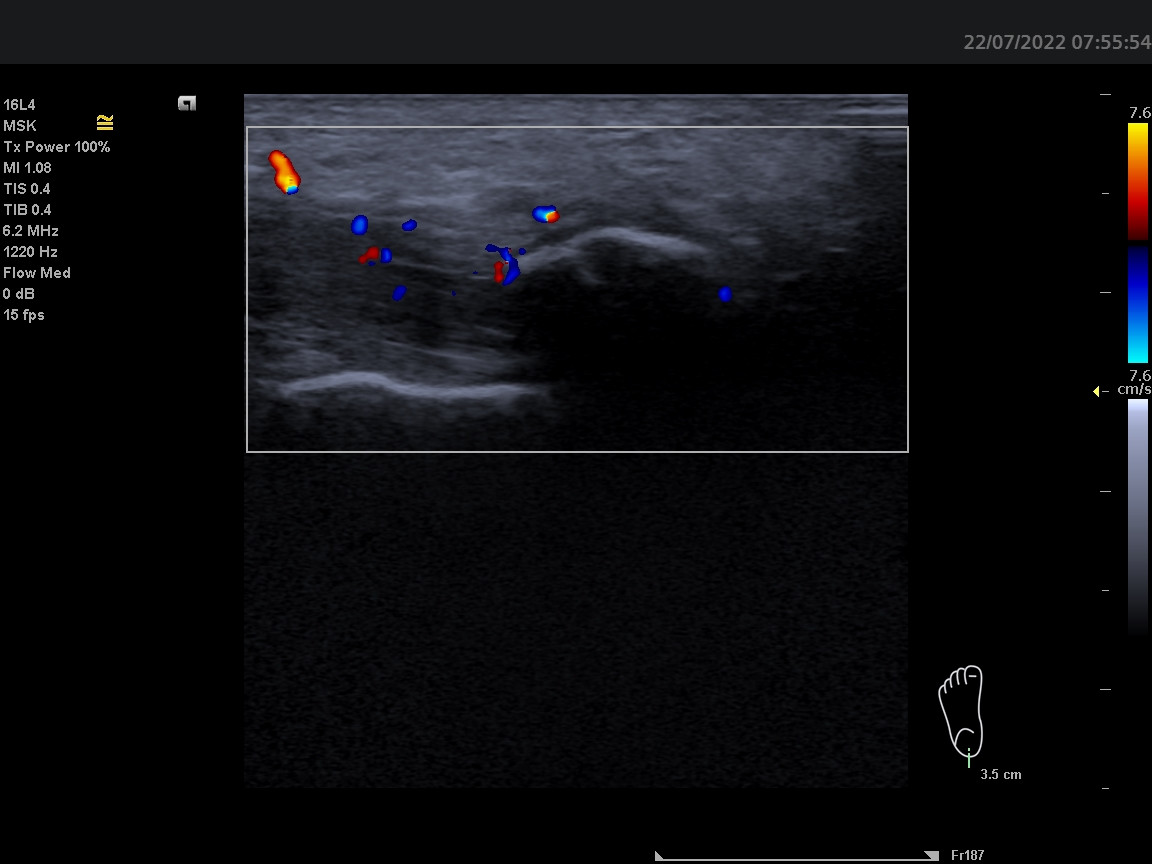

Dobrý den, ortopedem byla odeslána pacientka k revmatologickému vyšetření. 58 let, OA: HT, Psoriasis vulgartis, Asthma, HT, Barretův jícen - disp gastroenterologie. Pacientka si delší dobu stěžuje na úporné bolesti v oblasti úponu levé achillovy šlachy, dle Rtg 01/2022 dorzální i plantární patní ostruha - léčena ozařováním bez efektu. Sonograficky potvrzuji masivní patní ostruhu s mohutnými splývajícímí dopplerovskými signály v okolí i dále proximálně. Otázka: lze při této konstelaci výsledků odlišit primární psoriatickou entezitidu se vznikem masivního entezofytu od primární idiopatické patní ostruhy se sekundárním zánětem? Děkuji.

Z prosté zkušenosti mi na těchto snímcích pro jasnou entezitidu chybí hypoechogenita a zduření šlachy v oblasti enteze (zánětlivý projev) a PD signály pod 2mm od úponové kortikalis. Na snímcích chybí měřítko vzdálenosti, toto se tedy pouze domnívám. PD signály jsou ponejvíce okolo entezofytu a v proximálnějších částech šlachy. Tento nález bych hodnotila nejspíše jako tendinitidu Achillovy šlachy a masivní entezofyt, připomínajícím až Haglundovu exostózu.